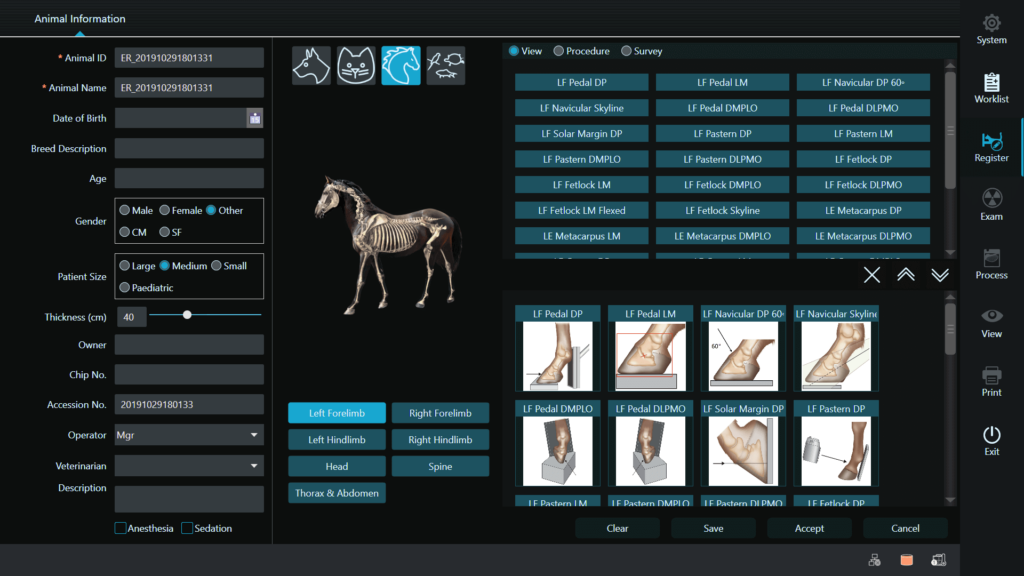

Veterinary Imaging Software

IQView veterinary software enhances the productivity of DR. The user-friendly interface combines with advanced image processing to quickly yield superior images. Available for use on desktops, laptops and tablets.

- Specialized exam menus for large or small animals

- Patient positioning guides

- Animal specific protocols

- Specialized measurement tools

- DICOM integration

Veterinary Imaging Software

With IQ View veterinary X-ray software, productive imaging is just a click away. The intuitive user interface is easy to learn and easy to use. Patient positioning guides and animal specific protocols make imaging simple and quick. Calibrated for use with EVS W DR Panels Series to give you excellent image quality with lower dose for confident results.